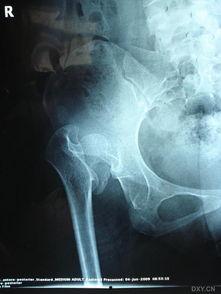

5. 髋关节脱臼接骨视频:髋关节脱臼是一种严重的关节损伤,这个视频教你如何进行髋关节复位。

5. 髋关节脱臼接骨图片:这张图片展示了髋关节脱臼的复位步骤,让你在紧急情况下迅速行动。